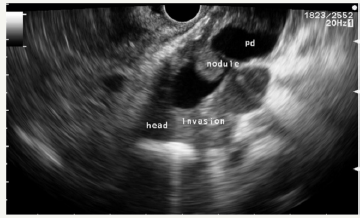

In the pancreas there are other, rare types of cystic tumors that can also be neoplastic or non-neoplastic [57]. Nonneoplastic pancreatic cysts include epidermoid [58] and dermoid cysts [59], duplication, retention, congenital epithelial and lymphoepithelial cysts [60]. The preoperative diagnosis of these types of cysts is extremely difficult [61]. Neoplastic conditions such as lymphangioma [62], hemangioma [63], cystic hamartoma, and acinar cell cystadenoma can manifest as cysts. Some solid tumors can undergo cystic transformation (adenocarcinoma, pancreatoblastoma, sarcoma) [64]. In addition, a number of neoplasms may be of a mixed morphological type. One such example is serous neuroendocrine neoplasia [48,65]. The pathology of the splenic vessels may also visualize like a cyst of the pancreas. In our practice, there was a giant aneurysm of the splenic artery, which at the pre-hospital stage was regarded as a pseudocyst of the pancreas (Figure 12A-12C). A similar clinical situation was described by Korean authors [66].

Figure 12A:EUS picture of aneurysm.

Figure 12B:Communication with splenic artery.

Figure 12C:Dopler color view.

Figure 12: Clinical case of aneurysm of splenic artery that was regarded as a pseudocyst on CT without contrast. Contrast wasn`t use because patient had chronic renal failure.